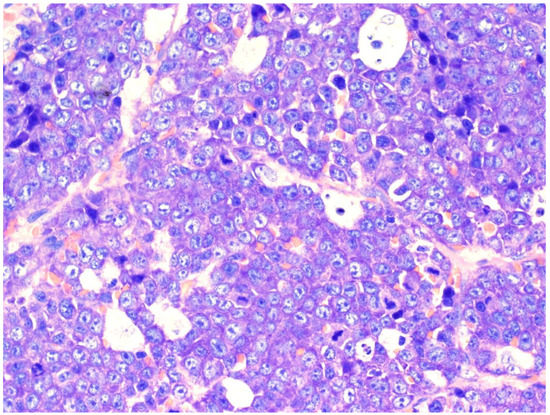

2. Diffuse Large B-Cell Lymphoma, Not Otherwise Specified

| Diffuse large B-cell lymphoma, NOS |